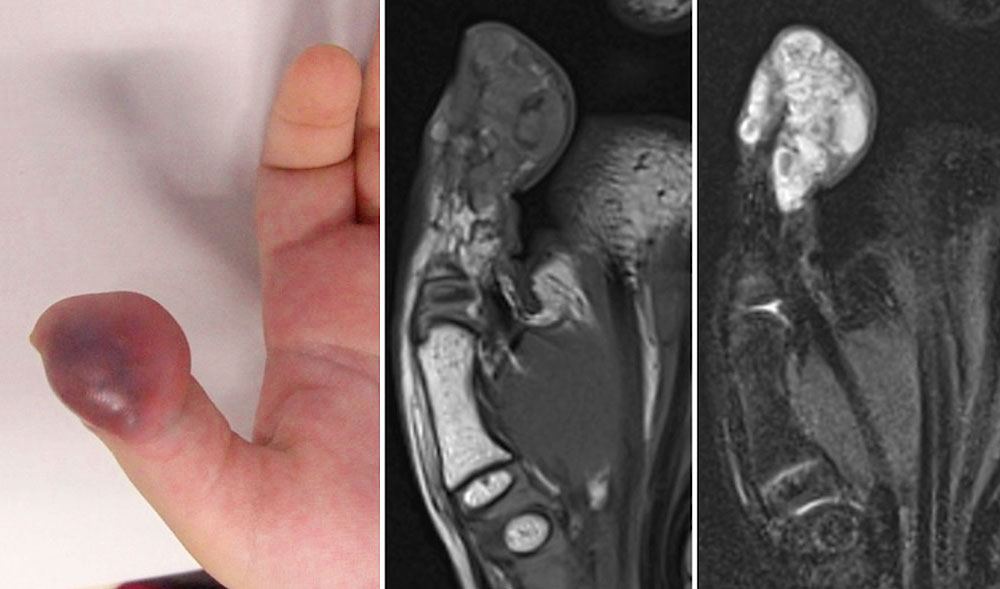

When superficial, thrombophlebitis may also look like a circumscribed hematoma appearing translucent through the skin. In this situation regression of thrombophlebitis is accompanied by changes in its color like a typical hematoma: initially dark bluish, then reddish and yellowish, then gone after a week.

Because of their frequency, especially in venous malformations, acute thrombophlebitides are often  visualized incidentally in magnetic resonance imaging (MRI) as part of treatment planning, since this imaging is often performed in symptomatic patients. Thrombophlebitis per se is not an indication for MRI. The fresh thrombi present as hypointense (black) in T2-weighted images as compared to the very hyperintense (white) venous malformation. In T1-weighted imaging, they vary in signal intensity and may be isointense or slightly hyperintense to the blood in the surrounding venous malformation. As a result of the inflammatory reaction of the thrombophlebitis, there may be significant local enhancement after contrast administration; in fat-saturated T2-weighted imaging, surrounding edema can then also be visualized.